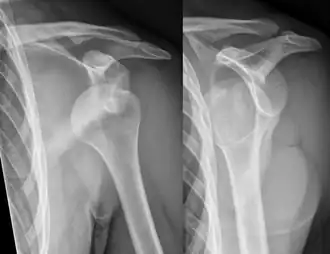

Передний вывих левого плеча. | |

Вывих плеча часто происходит в результате падения на вытянутую руку или на плечо[3]. Диагноз обычно ставится на основании симптомов и подтверждается с помощью рентгенологического исследования[2]. Вывихи плеча классифицируются как передние, задние, нижние и верхние, причем большинство из них являются передними[1][2].